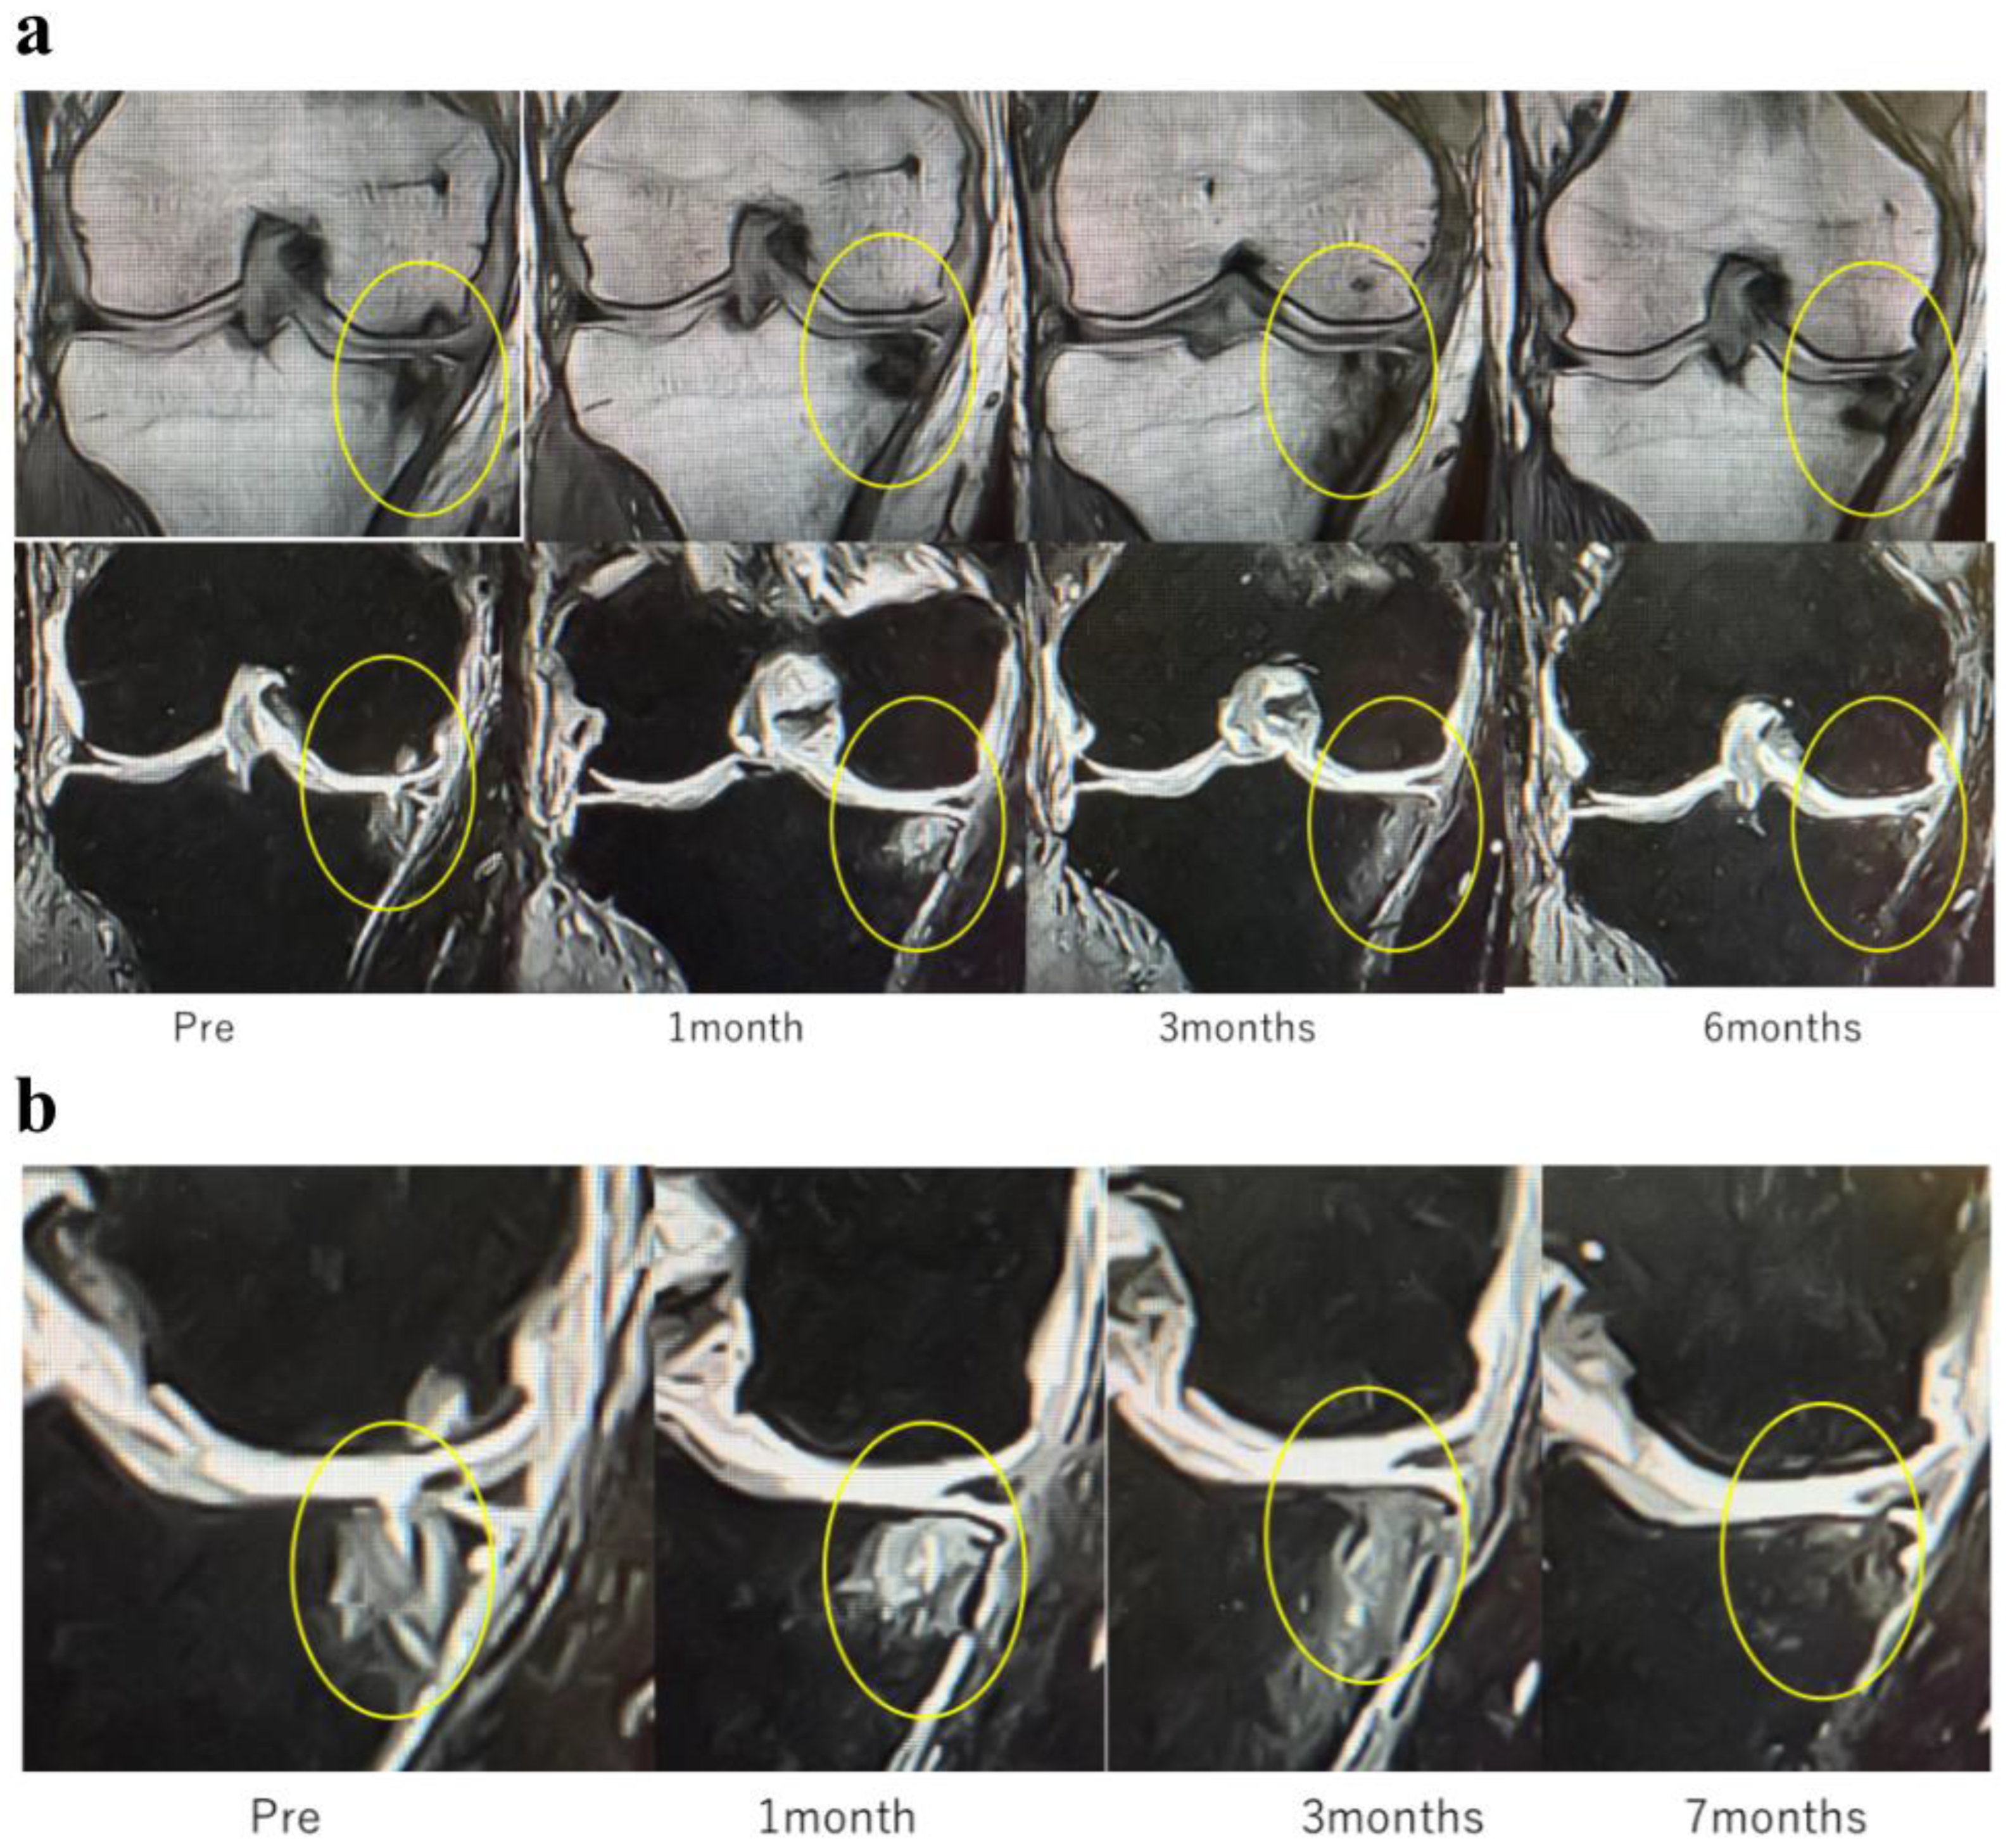

In Case 4 (Figure 9), a 63-year-old male, sequential MRI changes following combined treatment with intra-articular and intraosseous MSC administration and ESWT were evaluated. At baseline, irregularities of the articular surface and a tear of the SBP were observed. At 1 month, early signs of repair became evident, and at 3 months, further progression of structural restoration was noted. At 6 months, near-complete reconstruction of the articular surface and SBP was achieved. These findings suggest that the synergistic effect of MSC administration combined with ESWT may contribute to the regeneration of cartilage and subchondral bone (Figure 9a).

Figure 9.

(a) MRI changes after combined intra-articular/intraosseous MSC administration and ESWT in a 63-year-old male. T1-weighted coronal views (top row) and T2-weighted coronal views (bottom row) at baseline, 1, 3, and 6 months. The targeted area (yellow circles) demonstrated near-complete restoration of the articular surface and SBP at 6 months. (b) Detailed observation of lesions in T2-weighted images. Enlarged views of the joint surface from the T2-weighted images shown in Figure 9a. The BML and articular surface disruption observed pretreatment showed progressive repair at 1 and 3 months, with near-complete restoration achieved by 6 months.

These images (Figure 9b) represent magnified views of the joint surface from the T2-weighted images shown in Figure 9a. Pretreatment findings revealed a BML and disruption of the articular surface. Progressive repair was observed at 1 month and 3 months after treatment. At 6 months, near-complete restoration of the articular surface and SBP was evident.